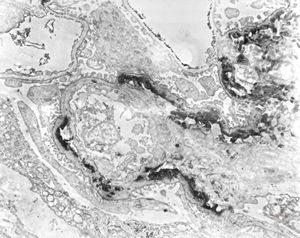

F,14y. | Alport syndrome - split and laminated, thick/thin basement membranes